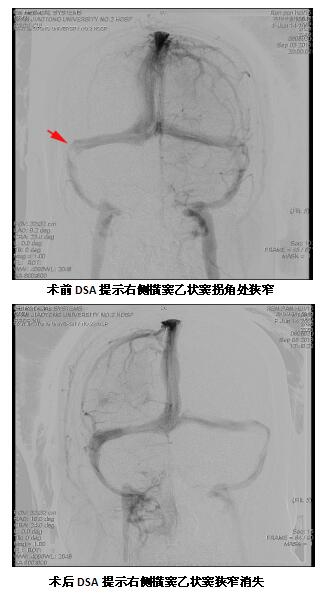

小任半年前出现间断性头痛,在当地医院按颈椎病予以对症治疗后未见明显好转,近5天出现双眼视力进行性下降,且双目失明,辗转当地及省内数家医院均未能明确病因,未求进一步治疗遂来我院就诊。经本院老师推荐,患者家属找到了神经外科许刚副主任医师,详细了解病史,仔细查体及研究已有的检查结果,初步判定患者为颅内静脉窦狭窄,导致的严重颅内高压继发视神经水肿导致患者失明。入院后立即予以抗凝、脱水、激素等对症治疗,并积极行全脑血管造影,造影结果证实了术前判断,患者为右侧横窦、乙状窦拐角处狭窄,经静脉窦测压发现狭窄远、近端压力差较大,有手术指征。经术前准备后由许刚副主任医师、僧志远主治医师、屈满丽护师在全麻下为患者行静脉窦狭窄支架成形术,术中顺利,术后患者诉头痛消失,术后2日患者双眼有光感,一周视力明显恢复,现出院3周,当地医院检查视力双眼均达到0.5。患者及家属非常感谢,说:“我们都觉得没有希望了,但你们却让孩子能够重见光明。”